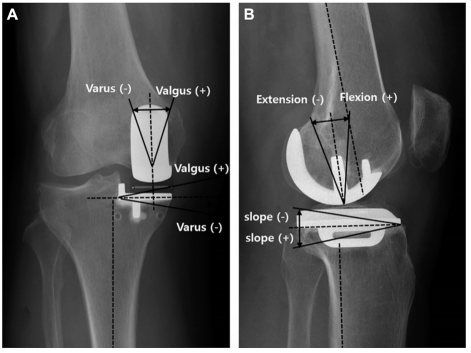

Cette étude était une étude monocentrique incluant des hommes et des femmes ayant subi une PUC médiale dans notre établissement de janvier 2008 à décembre 2017, et tous les patients ont subi une PUC en utilisant des méthodes standard. arthrite, déplacement tibial postérieur et instabilité.Les résultats cliniques et d'imagerie ont été obtenus à partir d'un examen rétrospectif des dossiers cliniques et des bases de données institutionnelles.Les angles coronal et sagittal fémoral (FCA et FSA) et les angles coronal et sagittal tibial (TCA et TSA) ont été mesurés sur des radiographies pour toutes les PUC à plate-forme fixe et à plate-forme mobile, comme indiqué.